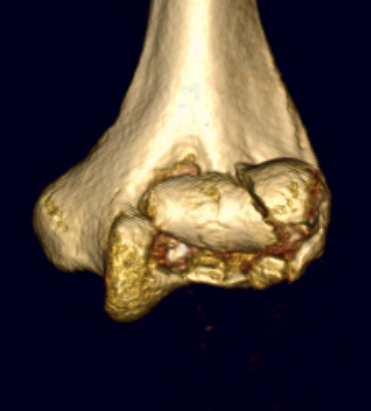

Coronal shear fracture of the distal humerus

Capitellum +/- trochlea

Dubberly Classification

Type I Type Ii Type III

Capitellar fracture

Capitellum + trochlea fracture

In one piece

Capitellum + trochlea fractures

In two separate pieces